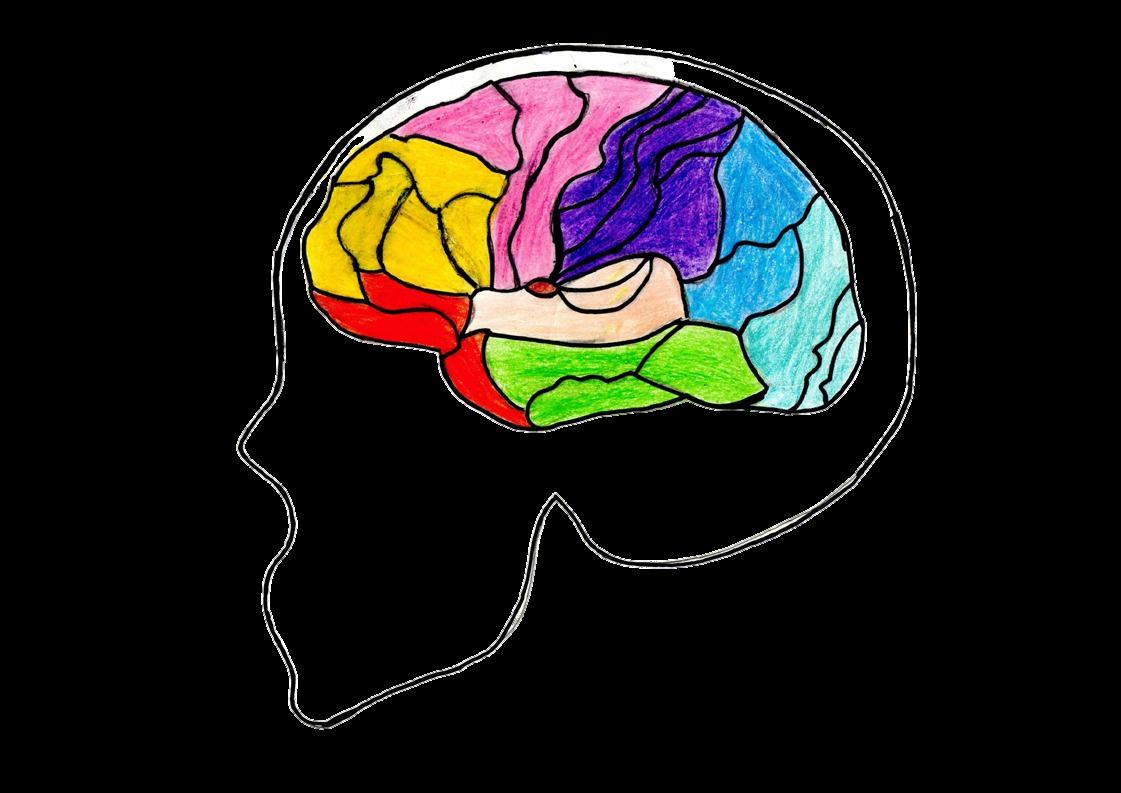

Cisura Parioccipital

Cisuras

Las cisuras o surcos del cerebro son cavidades que se forman entre los lóbulos cerebrales para así formar las partes que componen a la corteza cerebral, con el objetivo principal de crear más espacio entre la masa cerebral para acumular más fibras nerviosas

Áreas

Cisura de Rolando

Area pre frontal Area de Broca

Area de Wernicke

La corteza cerebral se organiza en diferentes áreas funcionales como las áreas sensitivas, motoras y de asociación Tiene una gran variedad de funciones, entre ellas la percepción e interpretación de la información sensitiva y la planeación e iniciación de la actividad motora

Area Auditiva

Cisura de Silvio

Visual

Area

Áreas de Brodmann Funciones Ejecurtivas Funciones Motoras Somatosensorial Atencion Funciones Visuales Memoria Regulacion emocional Sonido